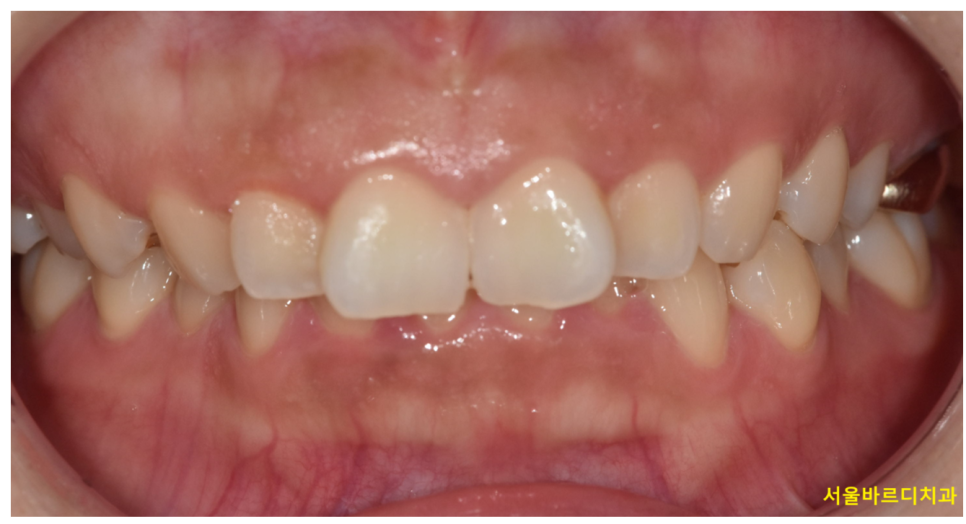

정상적인 교합 상태에서는

윗앞니가 아래앞니를 약간 덮고 있습니다.

그런데 지나치가 많이 덮는 상태를 과개교합

deep bite라 표현합니다.

보통 다음과 같은 모습이 관찰됩니다

이를 앙 물었을 때 아래 치아가 거의 보이지 않거나

윗니가 아랫니를 과도하게 덮는 모습이죠.